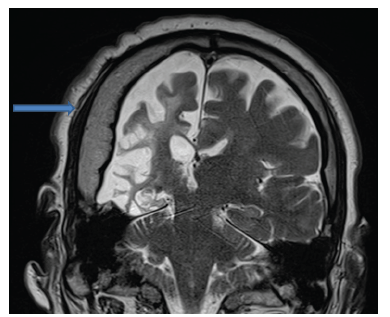

En los estudios complementarios, el paciente cuenta con electroencefalograma que evidencia actividad epileptiforme focal a derecha y episodios motores paroxísticos no epilépticos, y resonancia magnética de cráneo con protocolo de epilepsia (secuencias T2 coronal, FLAIR axial y T1 axial) que muestra una extensa disminución volumétrica en todo el hemisferio cerebral derecho, que se asocia a gliosis cortical y subcortical. Además, también se observó un engrosamiento compensatorio de la calota craneana y un aumento del tamaño del hemiseno frontal (figuras 1, 2 y 3).

T2 coronal

Figura 1: T2 coronal

Fuente: los autores con base en la historia clínica.